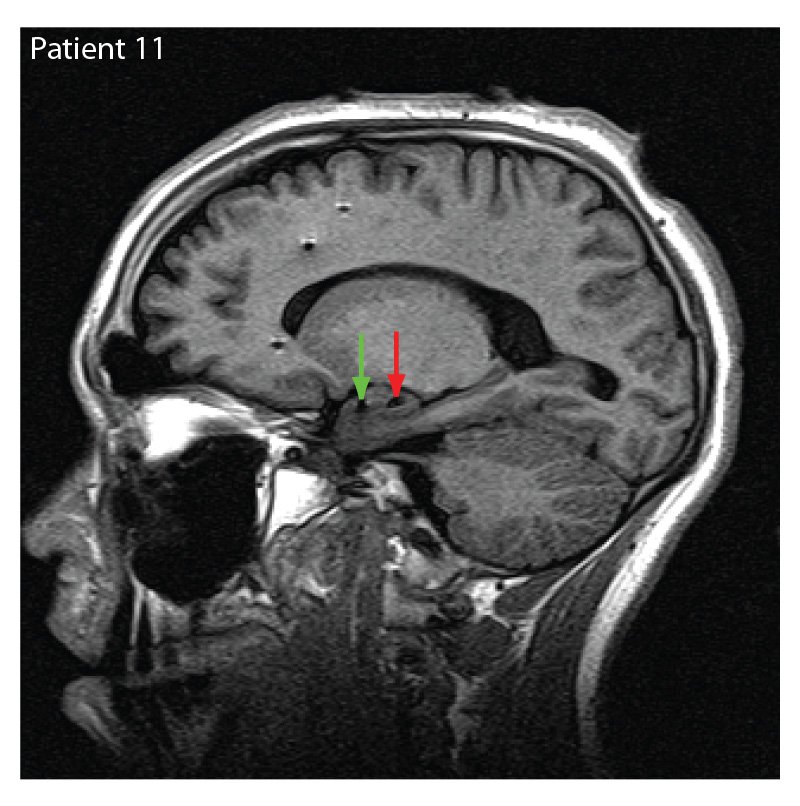

Evaluating another person's emotions based on facial expressions can sometimes be a complex task. As it turns out, this process isn't so easy for the brain to sort out either. Building on previous studies targeting the amygdala, a region in the brain known to be important for the processing of emotional reactions, a team of researchers from Caltech, Cedars-Sinai Medical Center, and Huntington Memorial Hospital in Pasadena, have found that some brain cells recognize emotions based on the viewer's preconceptions rather than the true emotion being expressed. In other words, it's possible for the brain to be biased. The team was able to record these responses from single neurons using existing electrodes—indicated by the arrows in the MRI image at right—placed in the brains of patients who were being treated for epilepsy. Participants were shown images of partially obscured faces showing either happiness or fear (see secondary image) and were asked to guess the emotion being shown. According to the researchers, the brain responded similarly whether or not the patient guessed the correct emotion.

Credit: Ralph Adolphs / Caltech